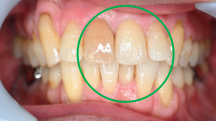

女性 Aさん 50代 (オールセラミック冠)

主訴

色が変わった上前歯をきれいにしたい。

治療内容

根管治療をし、オールセラミック冠を被せました。

所感

神経が取り除かれ、大きく詰め物がされていました。詰め物及び歯自体が変色し、虫歯になっていました。根管治療をし、ファイバーコアを入れ、オールセラミック冠を被せました。自分の歯は、捻転していましたが、被せ物により歯並びを改善することができました。

オールセラミック冠1本:¥104,500(税込)